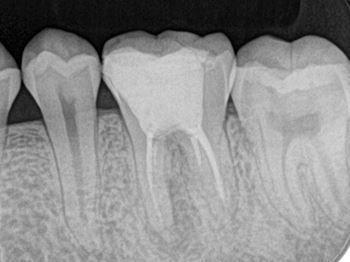

口腔外時間短縮と歯根膜温存を意識した術式:症例1-4

X線にて移植床形成量を確認

移植後の適合評価:症例1-5

レプリカと抜歯した右下8番との比較